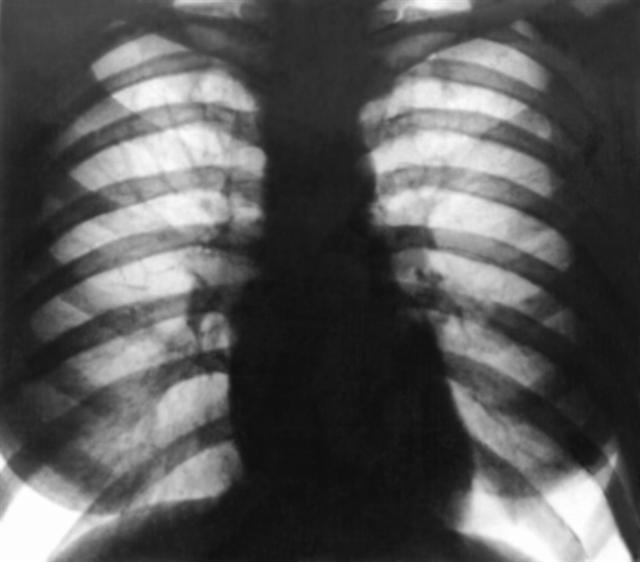

Рис. 10а). Рентгенограмма грудной клетки больного с митральным стенозом (передняя проекция): выбухания третьей дуги по левому контуру тени сердца, поперечник сердечной тени мал.